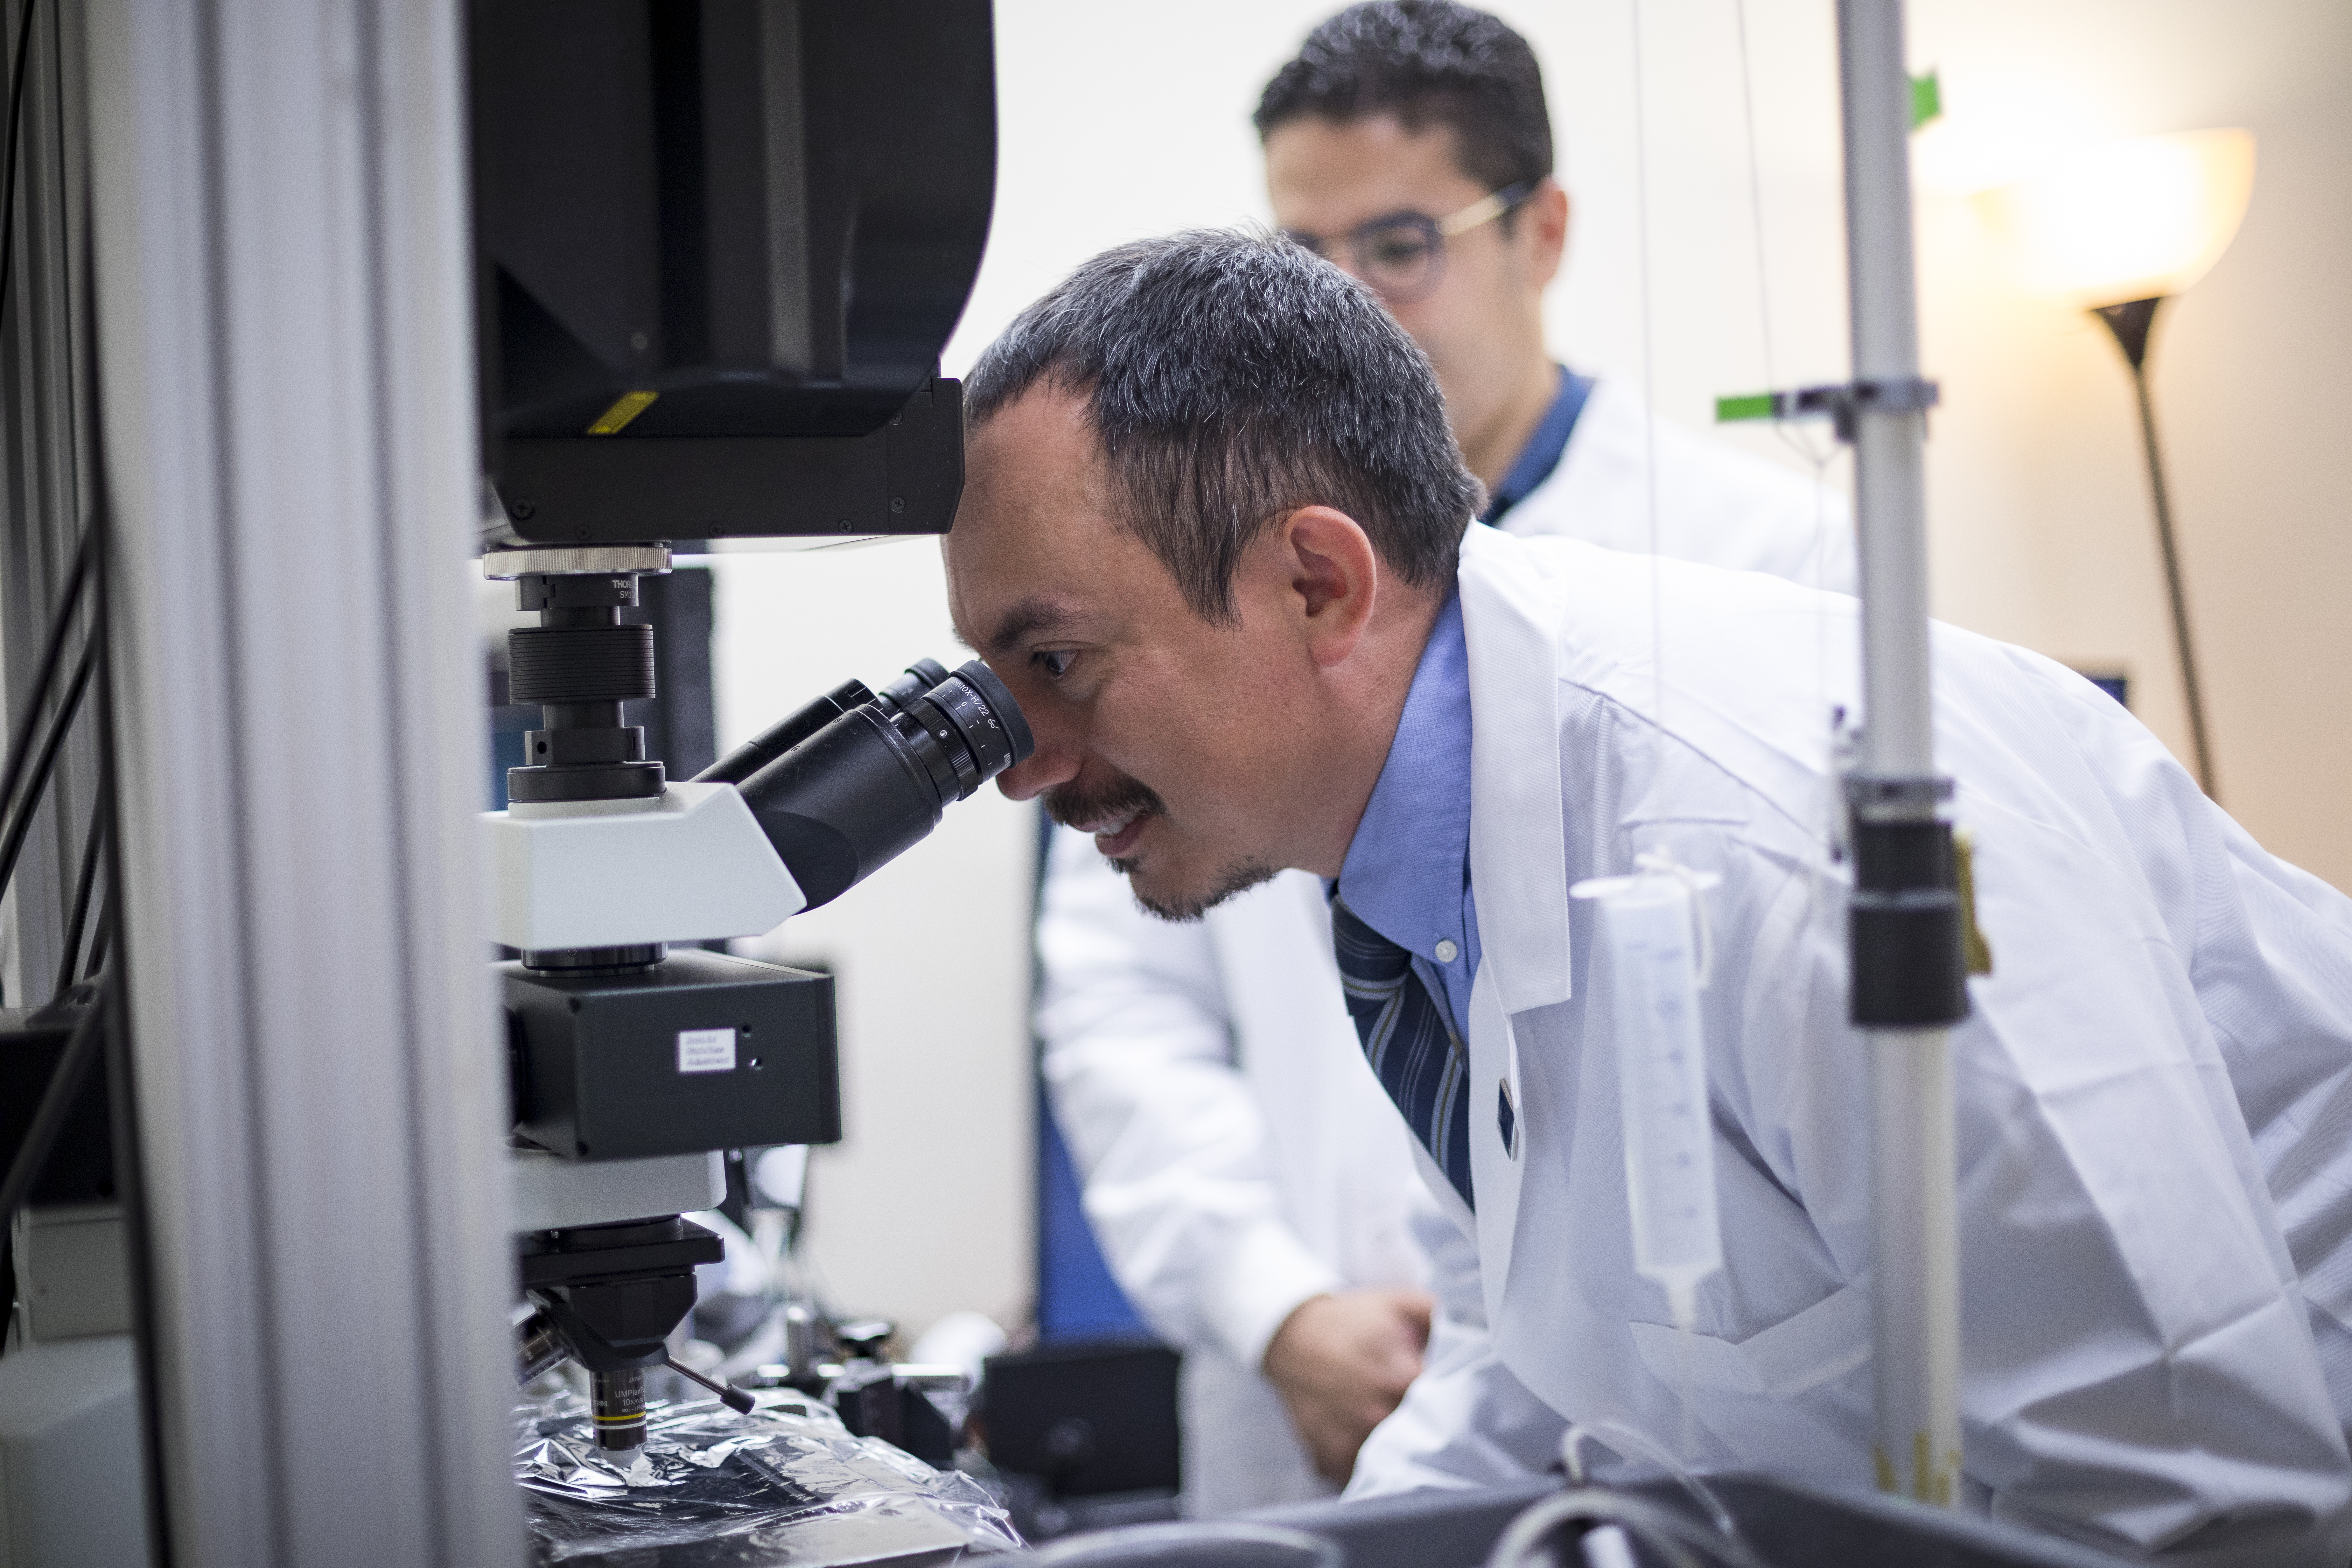

Over 50 Years of Bold Research

We believe that having the courage to invest in innovative ideas will lead to revolutionary therapies. Explore how the research we’ve funded has fostered life-changing breakthroughs across Alzheimer’s disease, macular degeneration, and glaucoma.

Accelerating Progress in Brain and Vision Science

Donate Now to Fund Critical Research

Your gift today can help drive innovation in Alzheimer’s, macular degeneration, and glaucoma research. By donating, you’ll support life-changing research and provide valuable resources for those affected by these devastating diseases. Give now to fuel hope and bring us closer to finding cures.